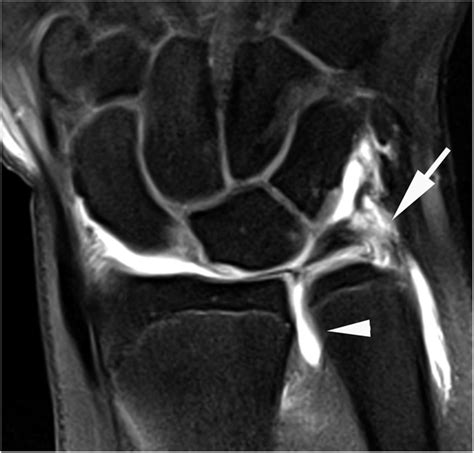

- Ligament tears: Particularly suspected injuries to the scapholunate or lunotriquetral ligaments.

- TFCC (Triangular Fibrocartilage Complex) injuries: Common causes of ulnar-sided wrist pain.